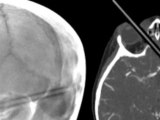

Dog saved after huge porcupine quill pierces into eye lid

2 Year Old Pierces Eye, Brain with Colored Pencil

Rescue pup has eye removed after porcupine quill attack